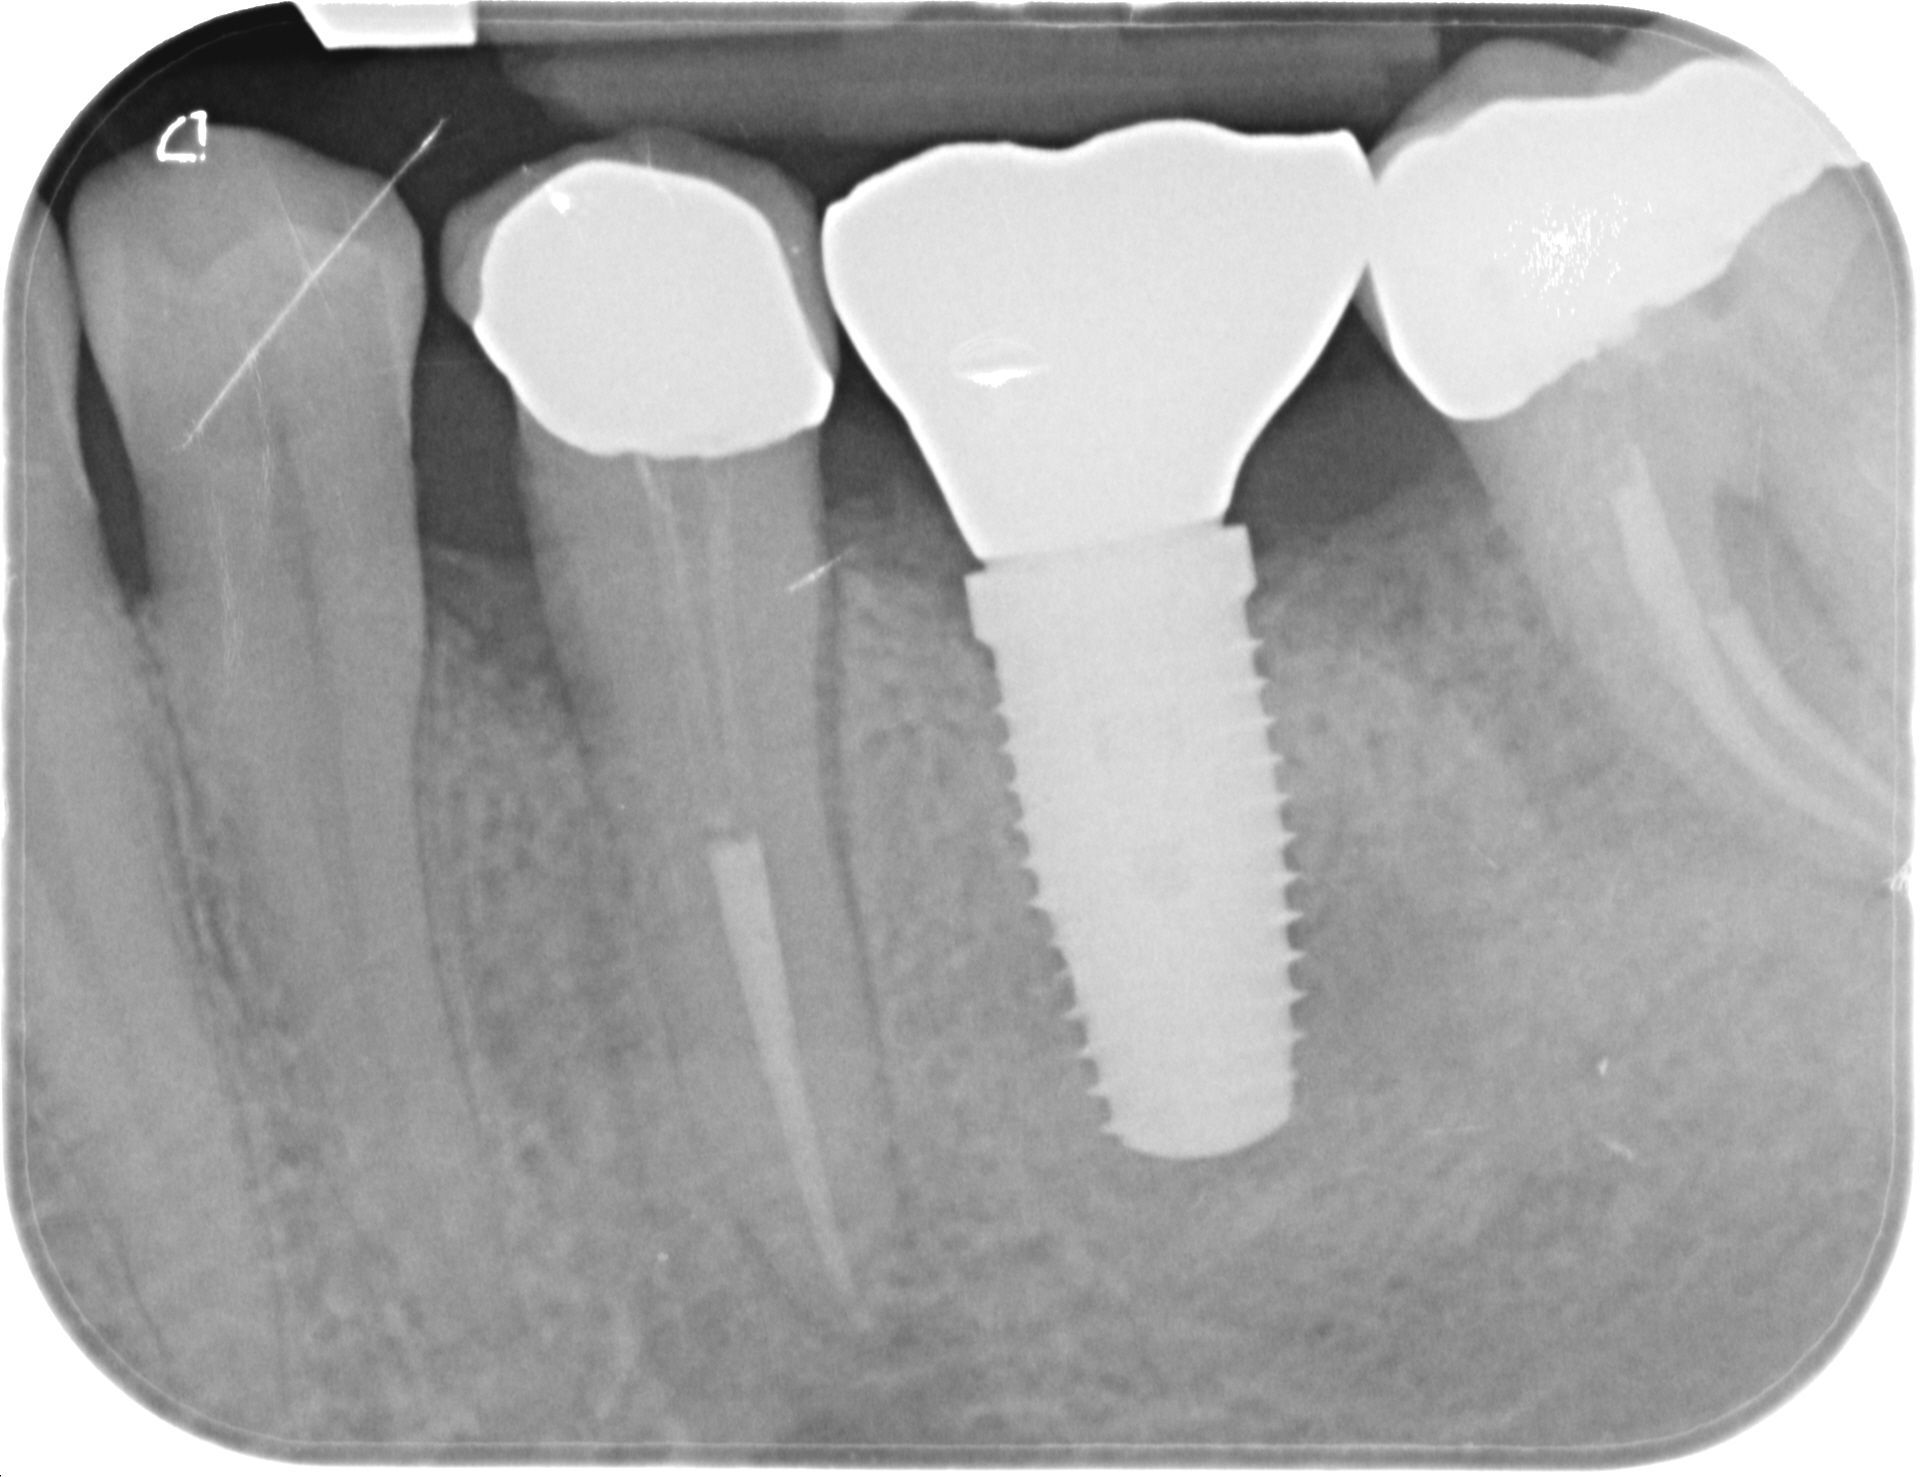

L’implantologia a carico immediato è una procedura con cui si fissa la protesi agli impianti dentale, viti in titanio puro o in lega di titanio e zirconio. L'impianto si avvita nell’osso, sotto la gengiva, e sostituisce a tutti gli effetti la radice dei denti naturali mancanti.

Agli impianti vengono, quindi, ancorati i nuovi denti fissi.